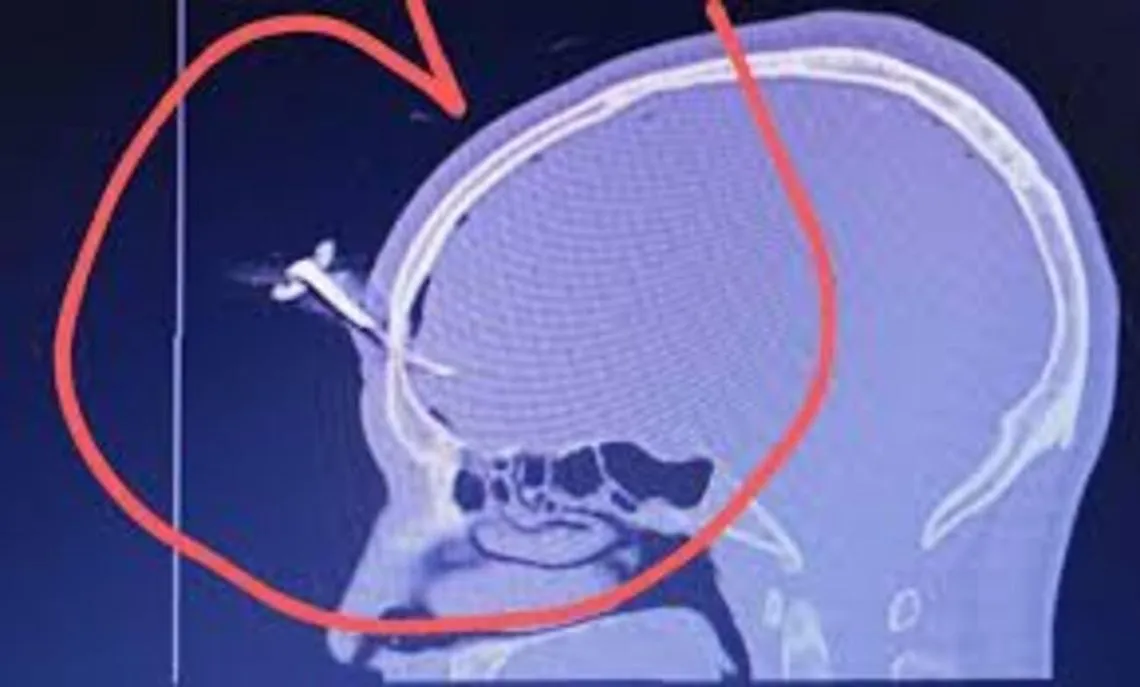

Ocurrió en un partido de fútbol femenino juvenil en Berazategui, cuando Jonathan José Smith sufrió la fractura de cráneo tras una ataque. Hay un detenido.